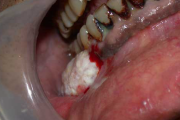

Aftoosne stomatiit

villikesest tekkinud haavand suu limaskestal